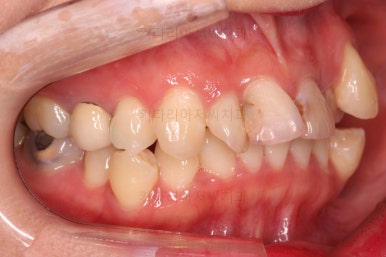

오늘 부산교정 키다리아저씨치과에서 소개해 드릴 환자분은 덧니, 치아상실(결손), 충치 등 많은 치과적 문제가 복합되어 있었던 분으로 충치치료 + 교정치료 후에 앞니 심미보철까지 진행했던 환자분입니다.

초진 시 입안의 모습입니다.

이미 썩어서 부러진 치아도 몇 개 보이고요.

많이 삐뚤어진 치아쪽은 양치가 힘들어 이미 많이 썩어 있는 상태에 덧니쪽은 잇몸도 많이 내려간 상태였습니다.

말그대로 교정치료 뿐만 아니라 전반적인 치료가 필요한 상황이었습니다.